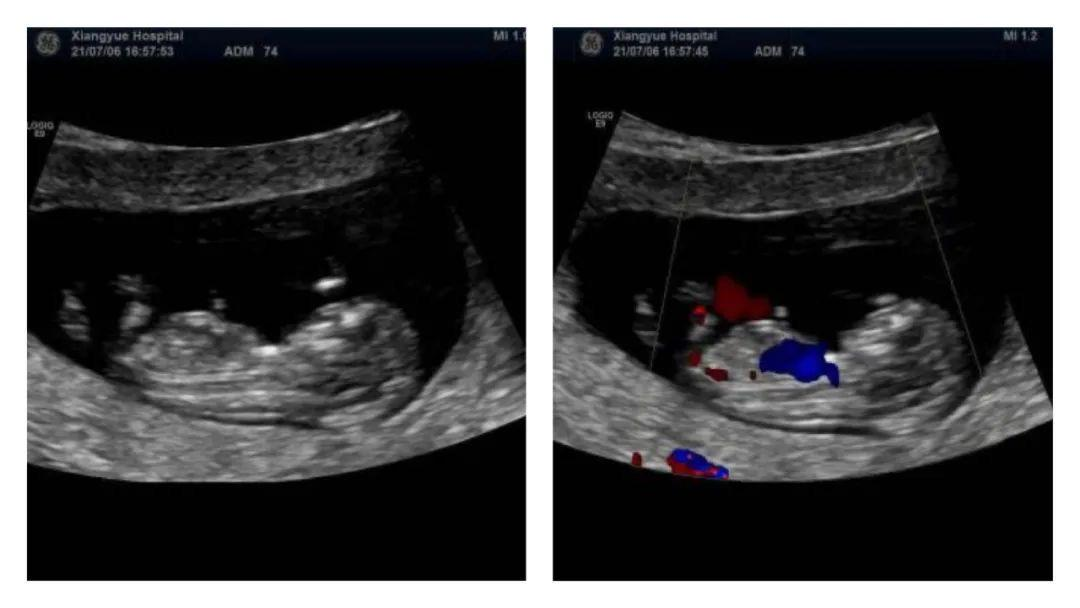

全称为“彩色多普勒超声”,是在B超的基础上增加了血流检测功能,最终成像也是黑白的。应用多普勒效应,能够捕捉到血管内血流的速度和方向,并以彩色编码的方式显示出来。

彩超对于心血管系统的检查尤为重要,可以了解血管内是否有狭窄和栓塞,以及评价心脏功能。若患者感到胸闷、心悸,通过彩超可以清晰看到心脏瓣膜的病变及血流动力学改变,为后续的精准治疗提供有力依据。此外,彩超在消化科、妇产科等方面也能够对疾病的鉴别和评价提供帮助。

总的来说,B超和彩超的主要区别在于彩超能够提供血流动力学的信息,而B超只能提供组织器官的结构信息。在实际应用中,彩超通常能够提供更全面的诊断信息。